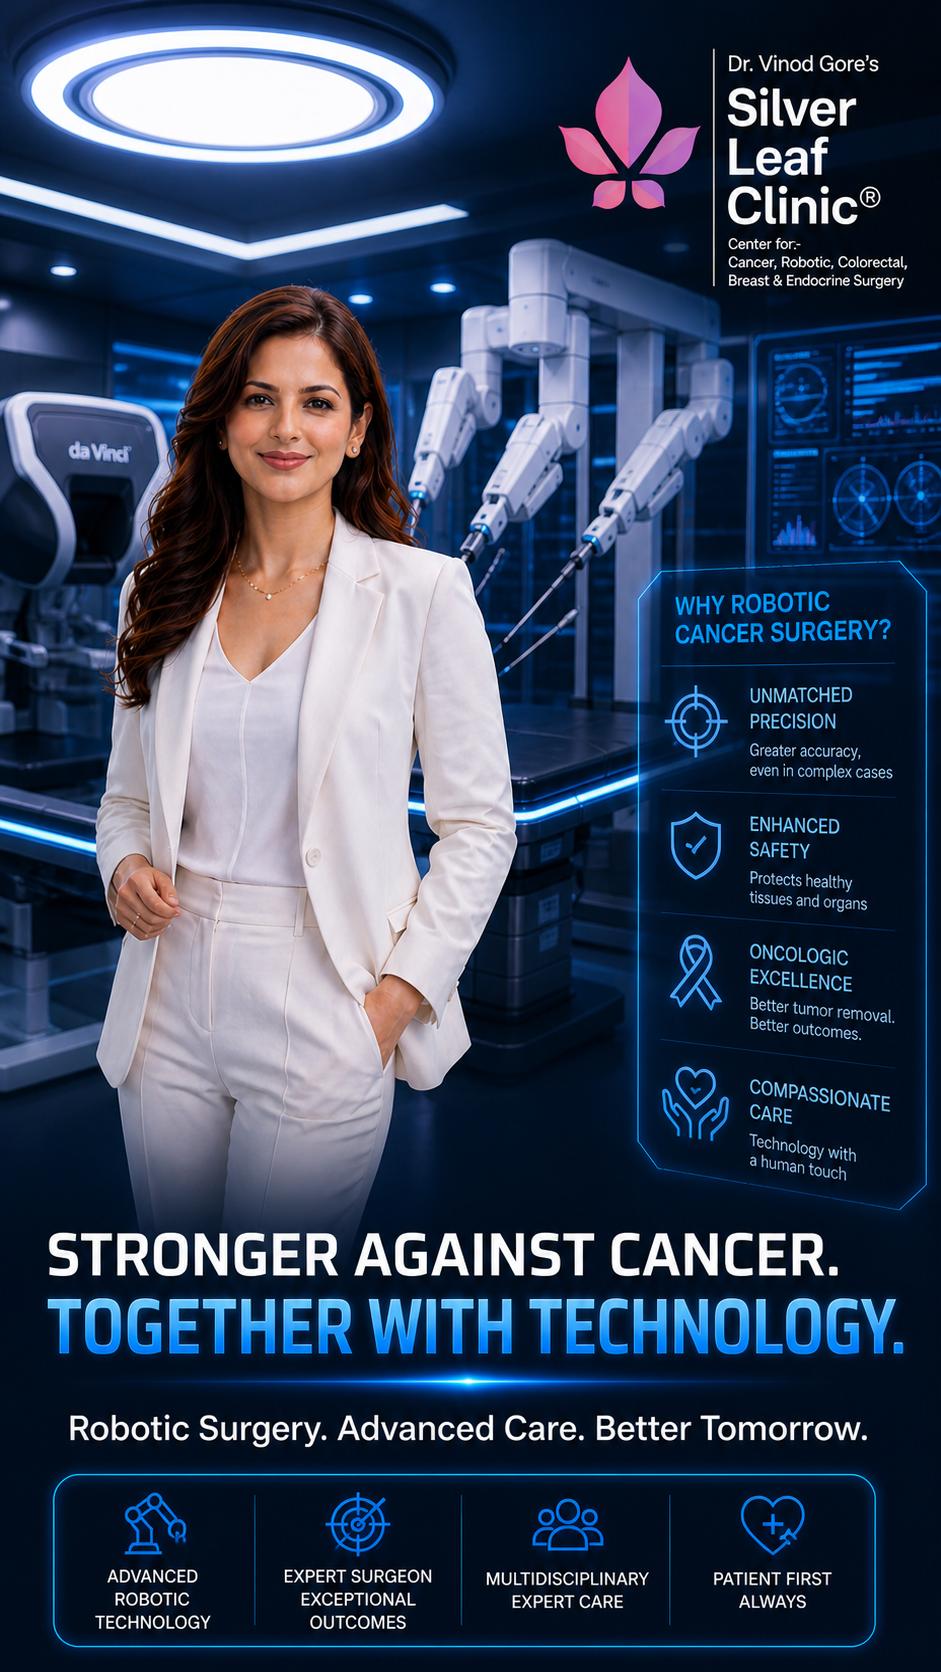

Don't Miss the Signs. Trust Robotic Precision

Take step confidently into a healthier future

Prioritize your well-being today